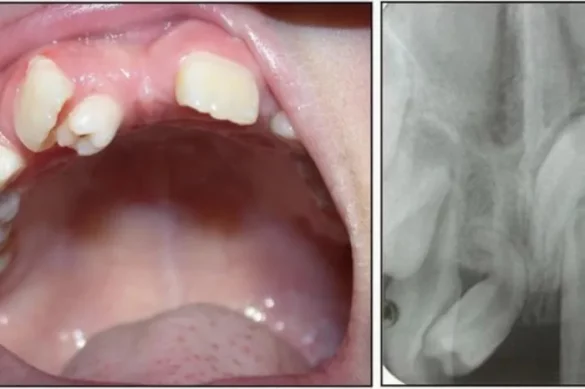

Malocclusion refers back to the fallacious alignment of the tooth and jaws. In kids, this could show up as crowded tooth, overbite, underbite, or crossbite. Malocclusion impacts the manner kids chew, speak, and easy their tooth. It might also reason pain and decrease self assurance of their smile. Genetic factors, oral behavior like thumb sucking, and early enamel loss can all make a contribution to malocclusion.

Pediatric dentists diagnose malocclusion thru cautious exam and dental X-rays. Early identity is essential due to the fact correcting minor misalignments in youth is regularly less difficult than treating excessive troubles later. Treatment alternatives encompass orthodontic home equipment which include braces or aligners, that are custom designed to every kid’s needs.